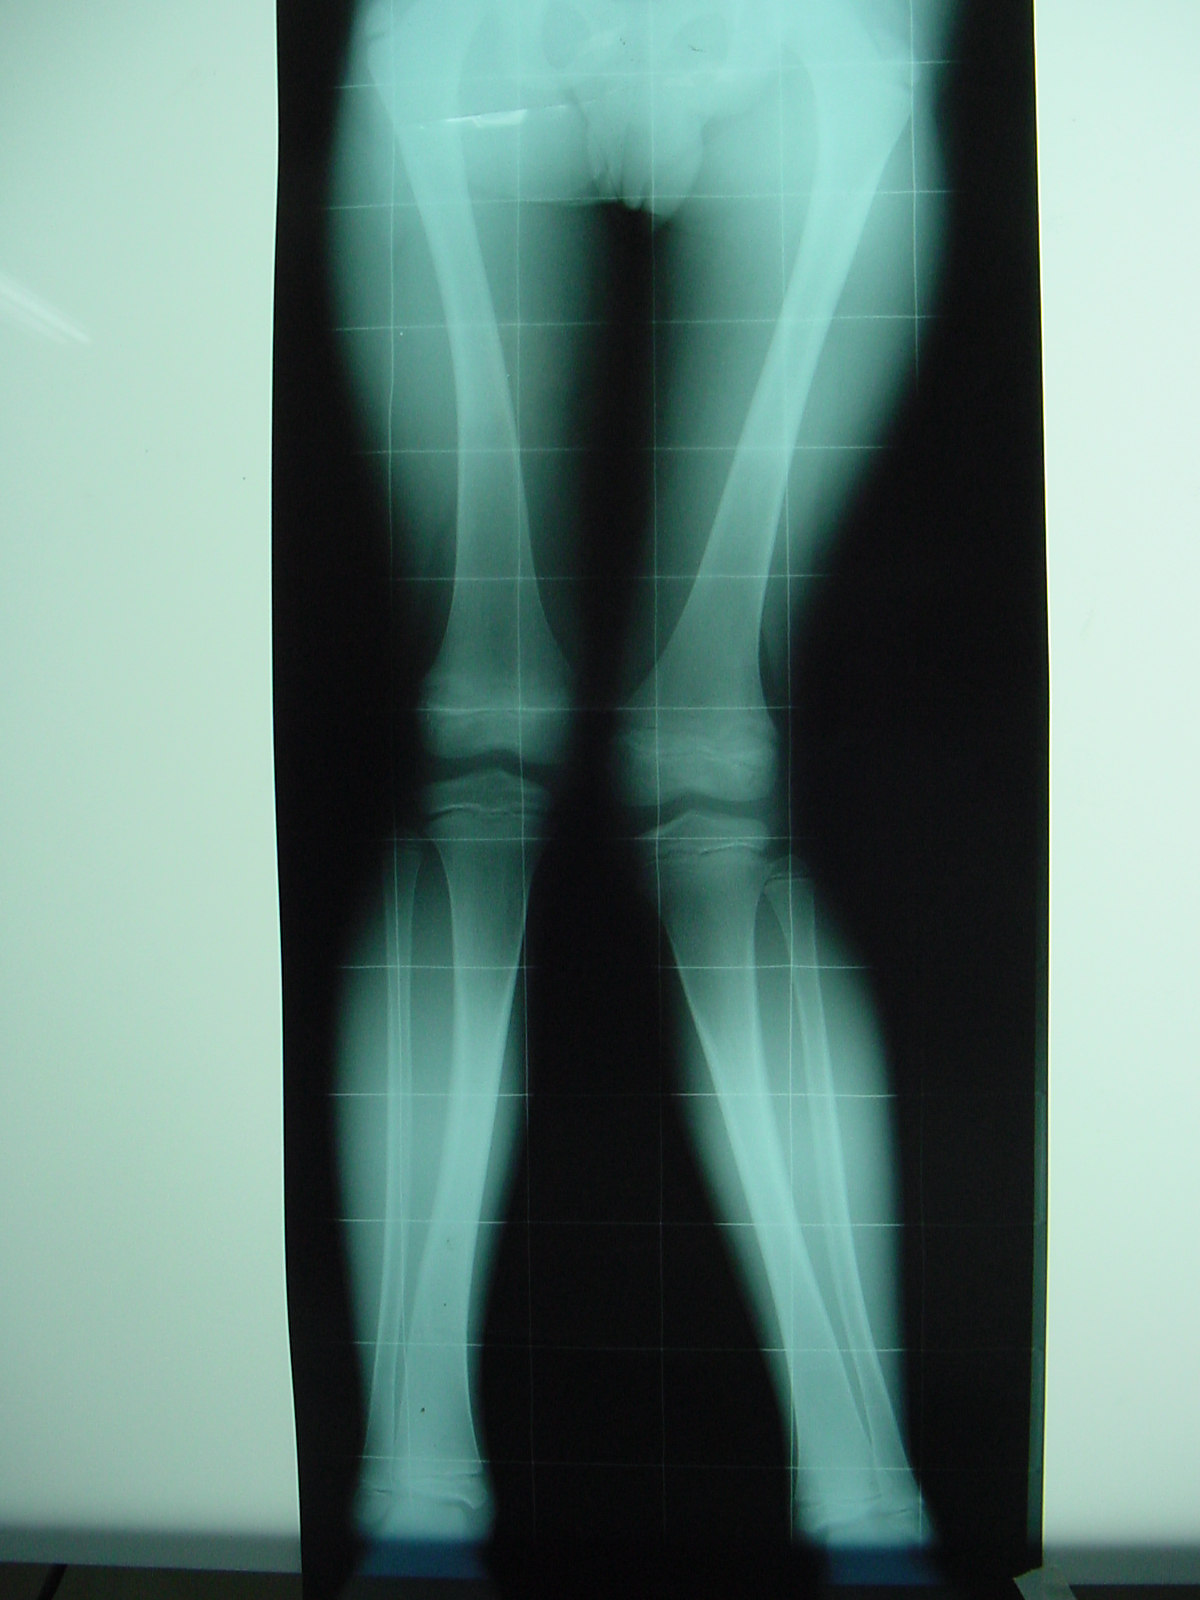

Growth Modulation in Renal Osteodystrophy